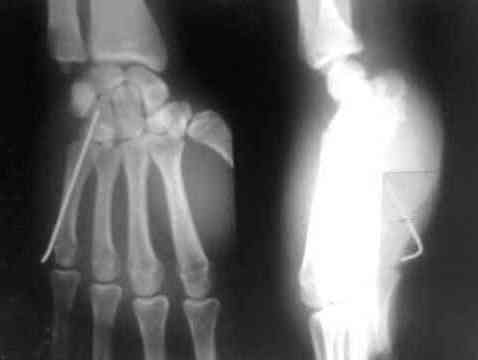

Дорогие коллеги, предлагаю посмотреть интересный случай. больной лечился в гипсовой лонгете 15 дней как ушиб.

правильный диагноз не был установлен.

поставил диагноз вывих 5 пястной кости.

больного я направил в область. его прооперировали. вынесены снимки.посмотрите.

после чего некоторые говорили что это можно было б и неоперировать, а оставить так.

что скажут на этот случай уважаемые колеги форума.